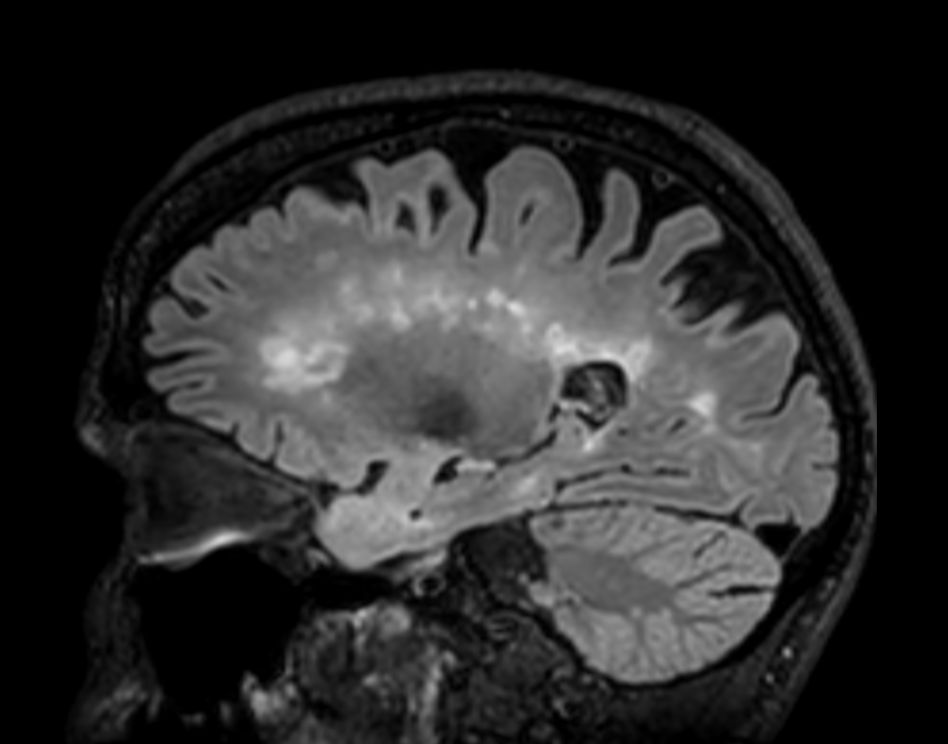

3D T2w FLAIR BrainVIEW Compressed SENSE

3D T2w FLAIR BrainVIEW (reformat) Compressed SENSE